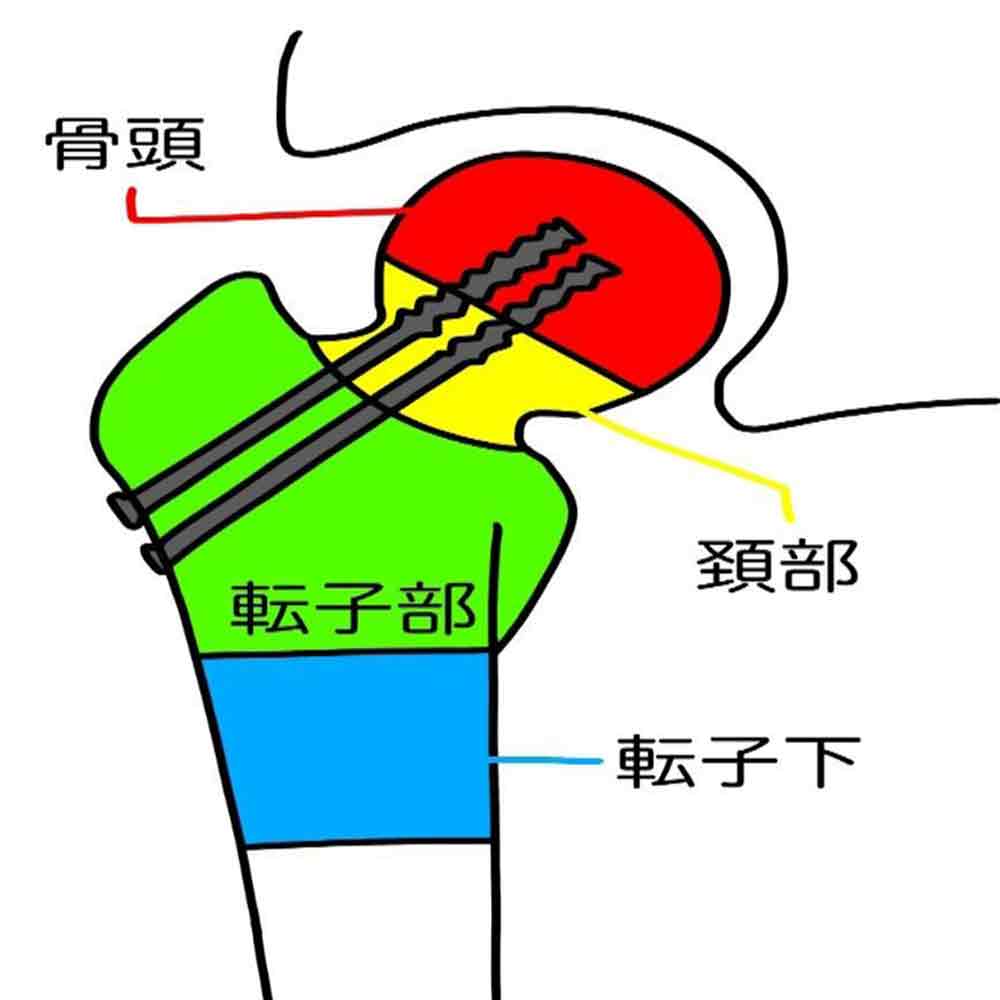

■ 大腿骨頸部骨折

【傾向】

大腿骨頸部骨折は、転倒や転落などによって大腿骨の根もとの部分が折れてしまった 状態です。40歳から年齢とともに増加し、70歳以上になると急激に発症率が高まります。また、約8割が女性です。

【発生原因】

高齢の女性よく見られるのは、女性の疾患に多い骨粗鬆症が年齢とともに進行し、骨が少しずつもろくなっていくことが大きな原因です。